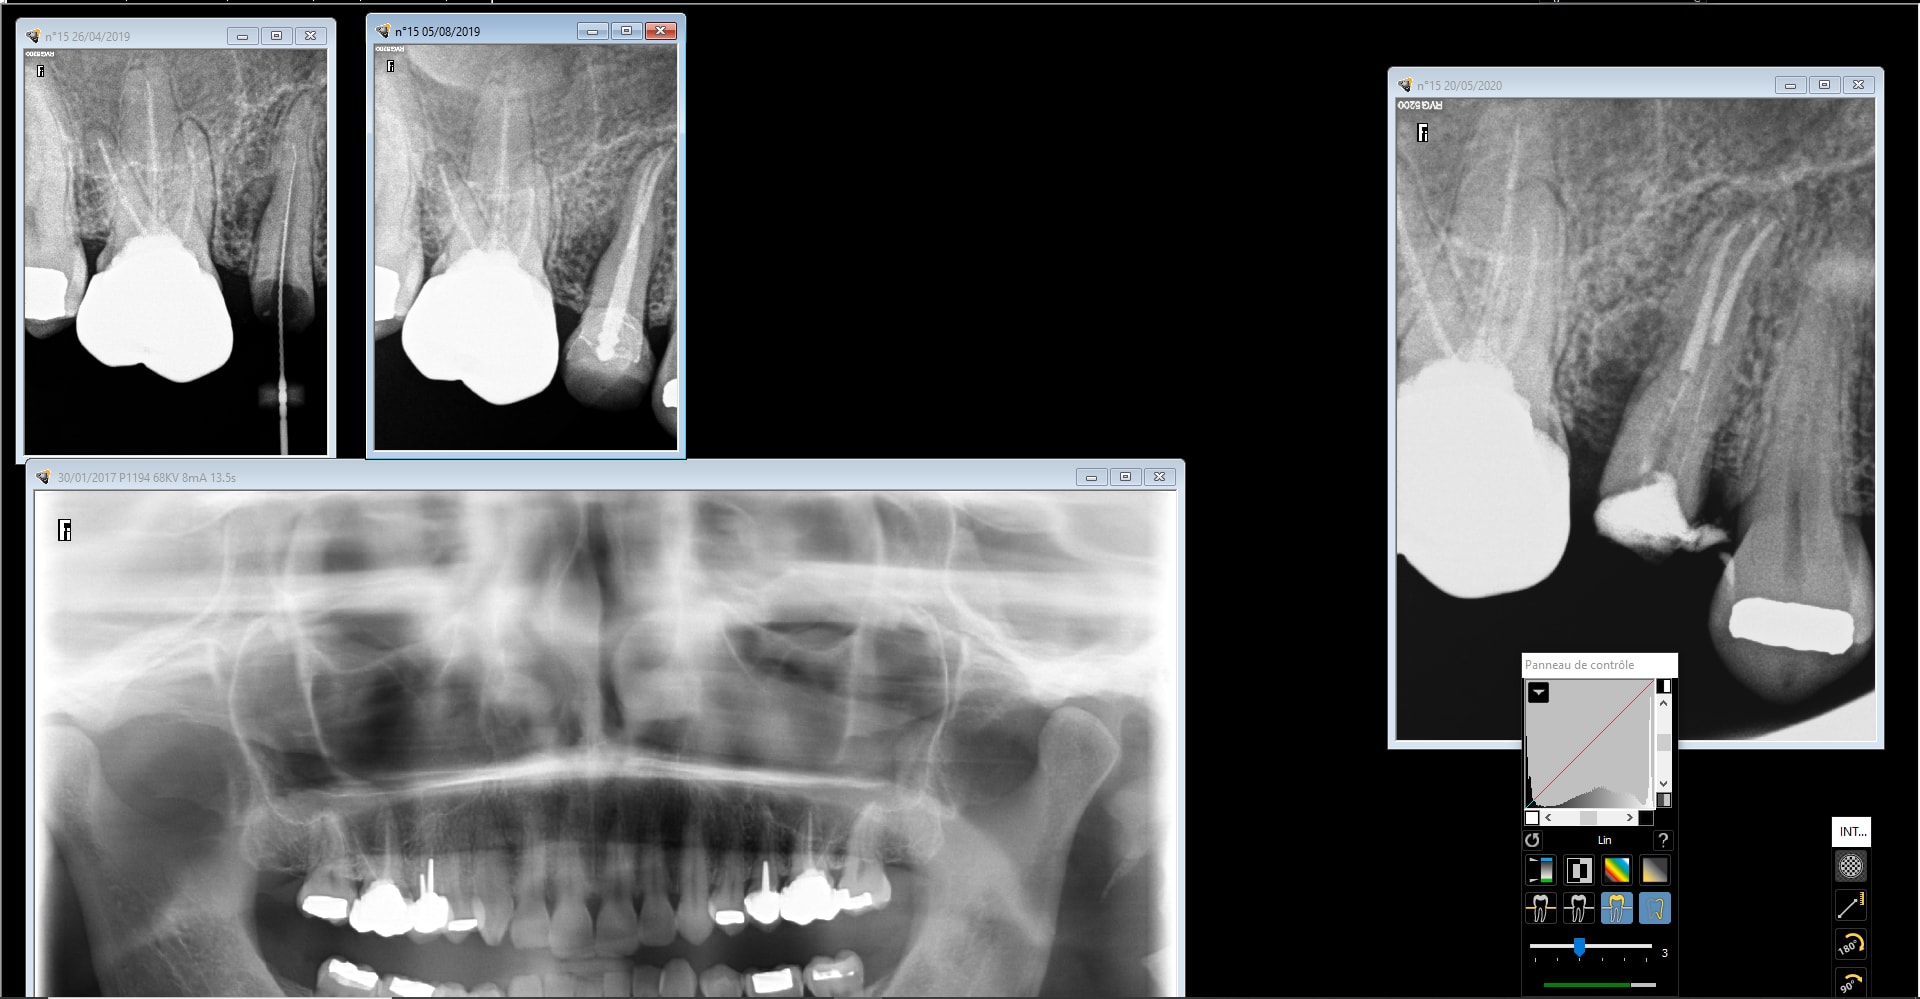

Dernier cas de ERI faite entre midi et deux. Au niveau historique, abcès 15 mars 2019, je retraite et je suis plutôt content ( merci au passage chicot qui m'a appris l'endo) et on temporise. L'image radio est toujours présente plus de 6 mois après avec fistule qui va et qui vient. Devis implant trop cher et donc je propose l'ERI. La suite en image. Je croise les doigts. J'ai positionné la dent un peu plus haut pour faire un style d'élongation coronaire, je ne sais pas si j'ai bien fait car la dent est quand meme plus mobile que bien enfoncée dans son alvéole...à suivre

et bien sur merci à enlay qui nous apprend l'ERI ( entre autre)!

Vu que tu as eu l'occasion de voir la racine de près, tu n'as pas vu une fêlure/fracture ? L'image latérale m'évoque ça en première intention surtout si ça guérit pas , comme ta reprise semble top.

merci. non pas vu de fracture. J'ai pensé plus à un canal latéral. La pro etant la depuis un an je pense que j'aurais eu une évolution de l'image osseuse tout autour de la dent+ descelllement. Comme je peux plus mettre les loupes avec ces visières de merde, je suis peut être passé à coté aussi... à suivre